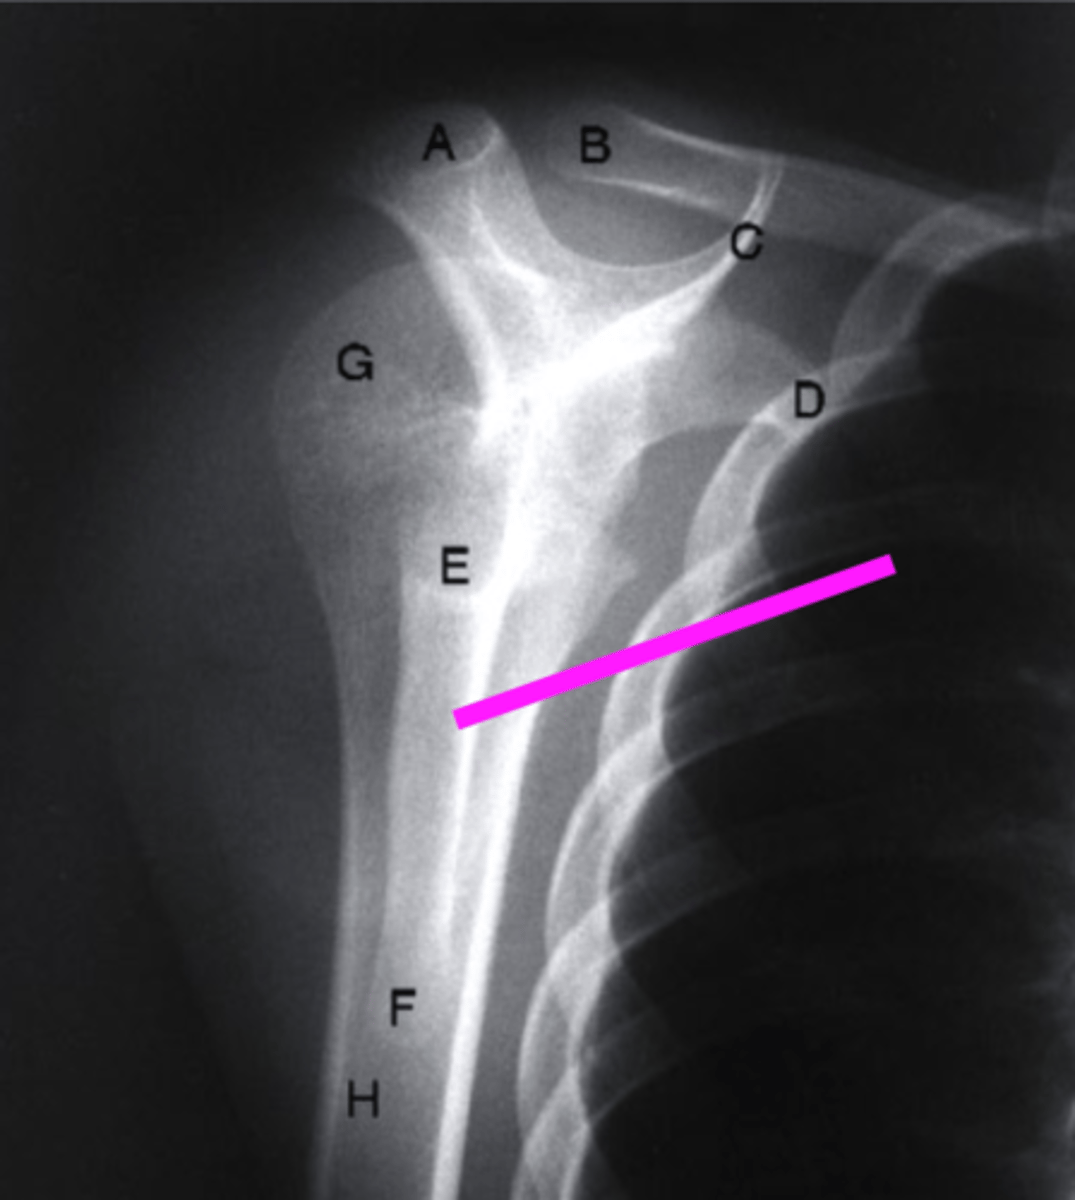

AP + ER

What view is this?

clavicle

what does the pink line point to?

spine of scapula

coracoid process

AC joint

acromion

Humeral Head

Greater Tuberosity

lesser tuberosity

Anatomic Neck of Humerus

Surgical Neck of Humerus

Shaft of Humerus

glenoid fossa

body of scapula

axillary border of scapula

vertebral border of the scapula